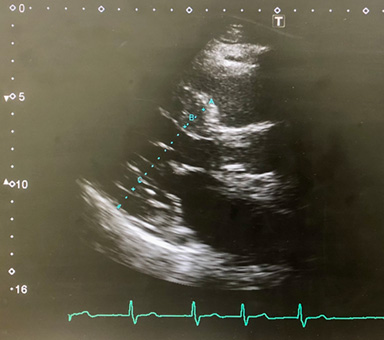

| 3. 心エコー |

○ |

心臓病のスクリーニング検査 |